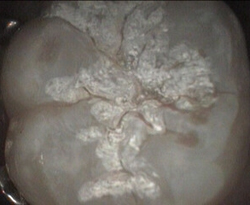

massive plaque build up disclosing 'red' tablet

immediate cleaning